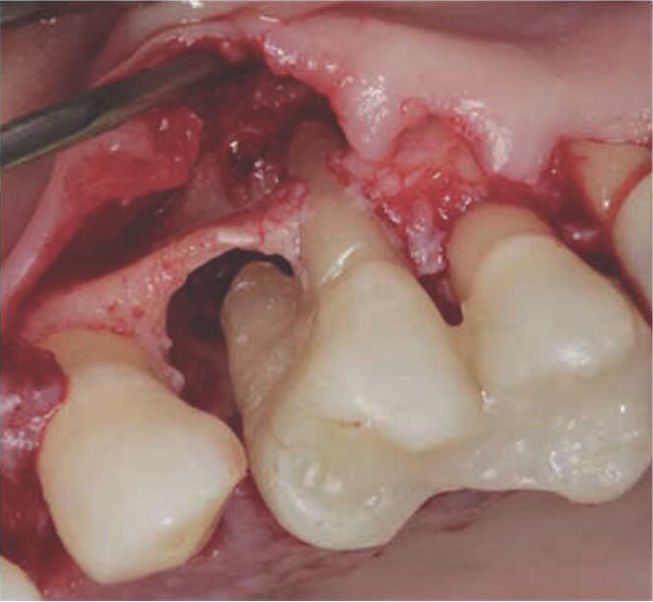

最吸引人的莫过于当天下午的手术直播(LIVE SURGERY)环节。来自意大利的著名专家G. Zucchelli医生和M. Stefanini医生将手术室搬到了ACTA, 现场高清直播一例种植体周围炎的手术。有意思的是,当缝合腭侧供瓣区时,由于缝合难度较大,Zucchelli医生缝合了几次才打结,结果被助手在剪线时剪断了线结,Zucchelli医生耐心地重新缝合,并幽默地说,“至少我可以示范一下怎样成功缝合!”

牙科疾病组 Davor Jurlina(来自克罗地亚)作品